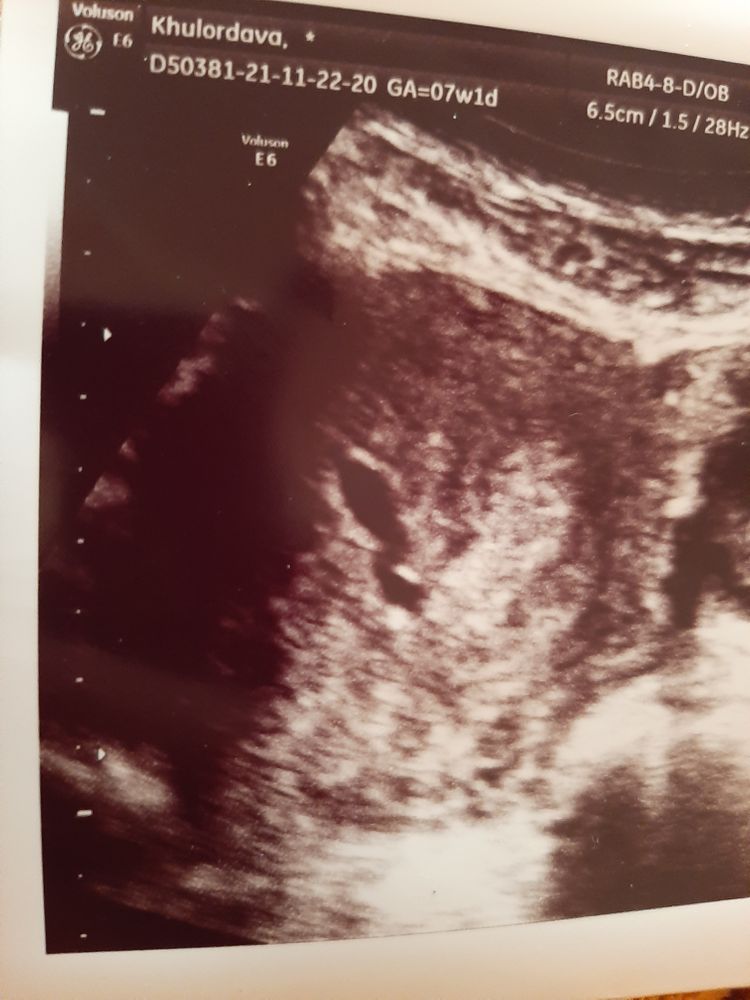

Реву 😭7 недель

Была на узи деформация пя узистка сказала иза тонуса. А врач долго не брал трубку когда взела сказала потом позванить поже . В 5 недель все было хорошо и жм был виден а сечас иза тонуса не могла увидеть. Как мне бить. Успокоитье меня у кого так было🙏🙏